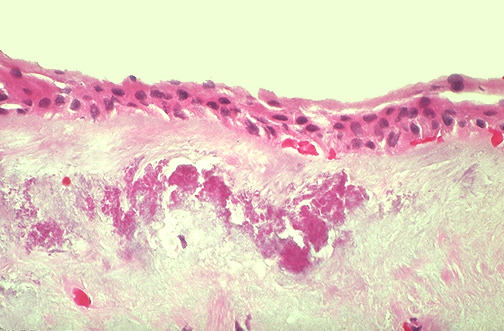

The microscopic appearance of a pterygium is shown here. Beneath the thinned conjunctival epithelium is an area of elastosis and basophilic degeneration of the substantia propria collagen. [Image contributed by Nick Mamalis, MD, University of Utah]